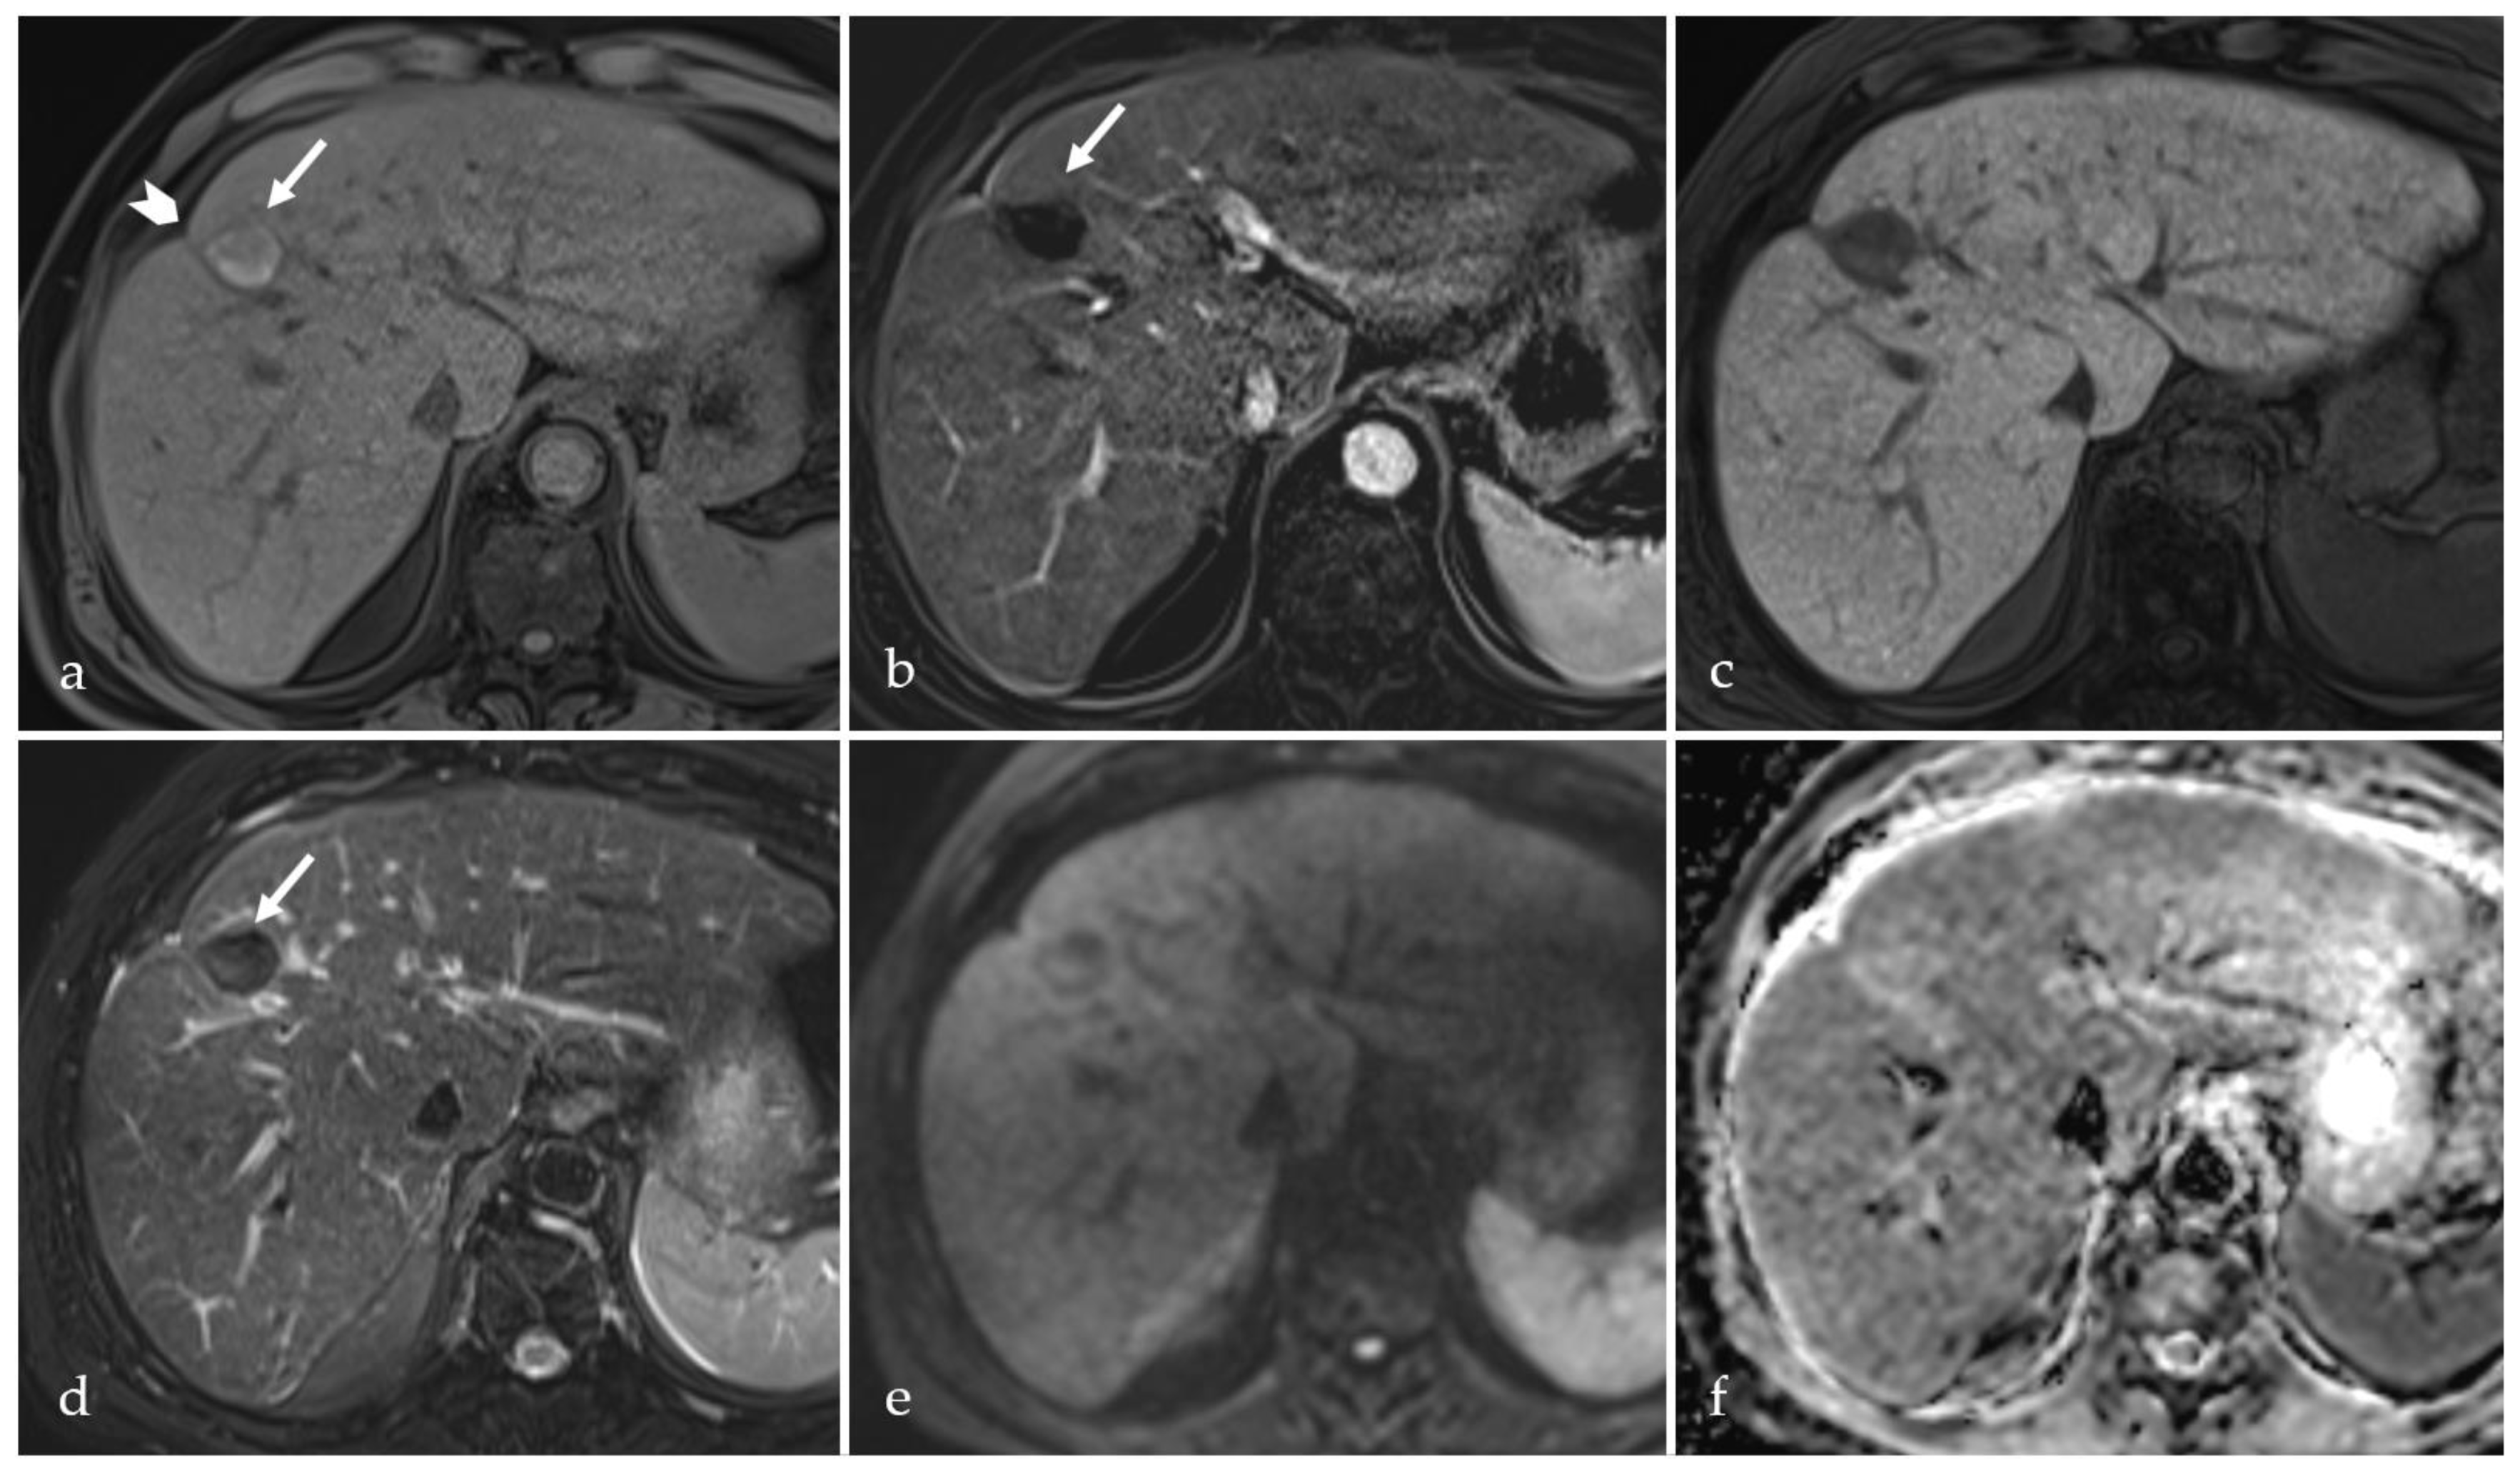

3.2. Expected Post-Treatment Imaging Features in the Absence of Viable Tumor Tissue

3.3. Transient Hyperemia